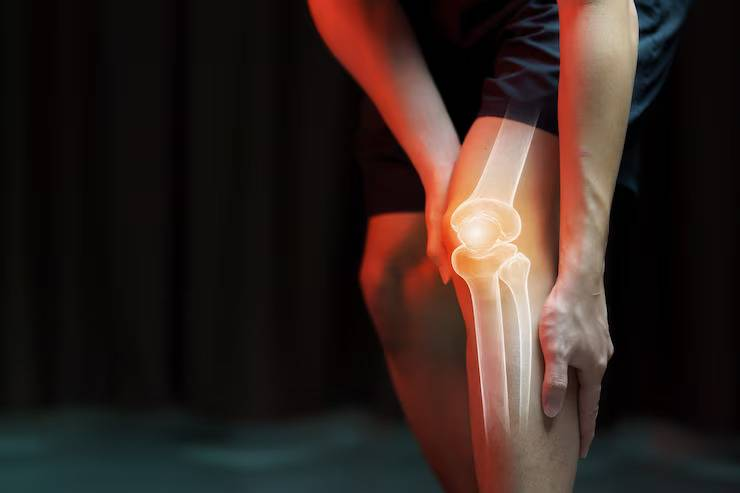

Dr. Ankur Singh is a highly experienced Senior Orthopedic Surgeon with over 15 years of expertise in Arthroscopy, Sports Medicine, Arthroplasty and Robotic Joint Replacement. He specializes in advanced knee, shoulder and hip surgeries, including primary, complex, and revision joint replacements, ligament reconstructions, cartilage restoration, osteotomy and joint preservation procedures.

Dr. Ankur Singh offers advanced orthopedic services focused on precise treatment, fast recovery and personalised patient care for effective bone and joint health.

Precise Orthopedic Care

We specialize in precise orthopedic diagnosis, surgical care, and recovery for all joint and bone conditions. Every step is led by expert hands in our clinic in Noida.